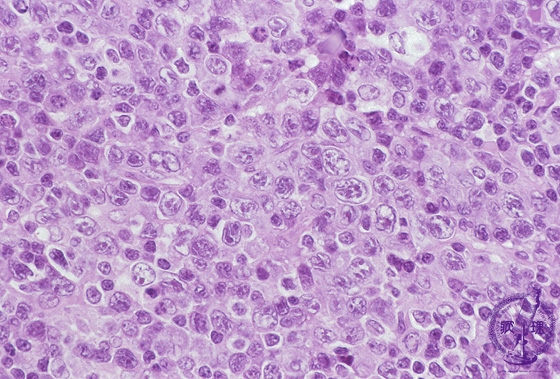

Microscopic image (H&E, high power view): A diffuse proliferation of large, exceedingly atypical tumor cells effaces the underlying lymph node follicular architecture.